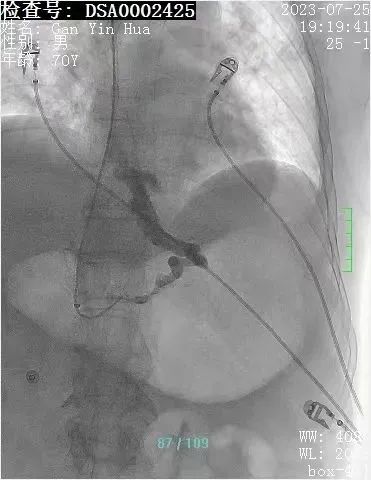

患者甘某某,男性,70岁,是一名乙型肝炎肝硬化患者,患者反复多次呕血,病情紧急,取得家属同意后,肝病科主治医师在科室人员的配合下,熟练进行门静脉穿刺、曲张食管-胃底静脉栓塞、门静脉球囊扩张以及支架植入术等一系列专业操作,约1个半小时,手术顺利完成,患者转回肝病专科进一步治疗后,好转出院。

经颈静脉肝内门体分流术(TIPS)被业内誉为“外周介入的技术高峰”,是借助介入器材,利用外科分流术的基本原理,达到治疗和预防食管-胃底静脉曲张破裂出血和顽固性胸腹水等门静脉高压并发症的一种治疗方法,对于急性消化道出血的高风险肝硬化患者来说,早期应用TIPS可以提高患者的生存率,降低再出血的发生率。